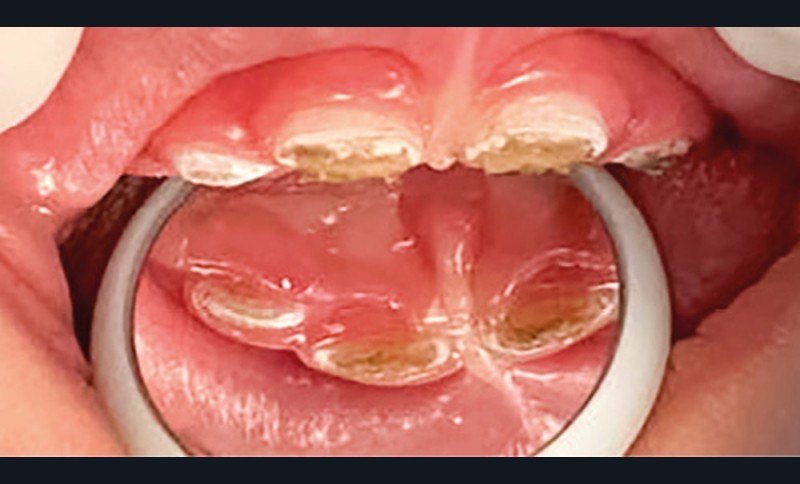

- L’évolution de la maladie carieuse : cette pathologie bactérienne, multifactorielle, se transmet très vite d’une dent à une autre dans la cavité orale de l’enfant. Ainsi, avant l’âge de 6 ans, la carie précoce de l’enfant (CPE) peut atteindre un stade sévère et ne plus permettre à l’enfant de mastiquer sans douleur (fig. 2).

- La perte de chance pour le développement : la CPE non traitée va entraîner l’avulsion précoce de certaines dents, induisant des troubles alimentaires pouvant se répercuter sur le développement général de l’enfant (croissance et développement cognitif), voire de sa vie sociale (absences scolaires répétées, pas de sourire). La CPE a un impact négatif sur la qualité de vie de l’enfant.